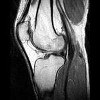

МРТ детского сустава используется в детской травматологии и ортопедии, ревматологии и онкологии для выявления травматических повреждений, воспалительных и опухолевых поражений суставов и окружающих мягких тканей. МРТ является единственным неинвазивным методом визуализации компонентов мягких тканей сустава: связок, сухожилий, хрящей, периартикулярных мешочков. Показания МРТ сустава для ребенка могут включать в себя травмы передней части, боль в проекции сустава, отек, покраснение, снижение подвижности В педиатрии МРТ исследует височно-нижнечелюстные суставы, плечи, локти, колени, бедра, лодыжки, ступни и кисти рук.

Обследование определенного анатомического региона имеет свои показания, определяемые детским специалистом. МРТ тазобедренных суставов ребенку проводится при подозрении на дисплазию (врожденный вывих бедра), артрит, перелом головки бедренной кости, остеомелит. С помощью МРТ коленного сустава у ребенка могут выявляться повреждения связок (передней и задней крестообразных, коллатеральных, собственной связки надколенника) и сухожилий, разрыв мениска, перелом надколенника, гонартроз, бурсит, артрит, болезнь Шляттера ). МРТ голеностопного сустава ребенку может назначаться при переломе голеностопа, разрыве связок. Исследование плечевого сустава ребенку с помощью МРТ проводится при привычном вывихе, разрыве капсулы или вращательной манжеты плеча, ущемлении сухожилий и нервов Проведение МРТ лучезапястного сустава ребенку показано при повреждении связок, переломе ладьевидной кости, отрыве шиловидного отростка локтевой кости МРТ височно-нижечелюстного сустава ребенку востребовано не только в травматологии (при переломах нижней челюсти и височной кости, излитии крови в полость сустава), но и в стоматологии (при планировании ортодонтического лечения).